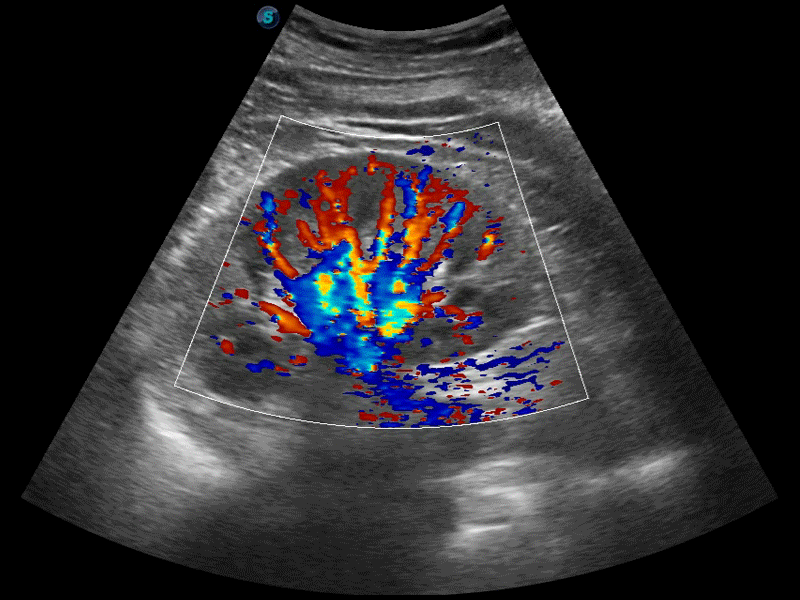

高分辨率血流成像技術提高了對低速血流信號的檢測能力。在提高空間分辨率的同時,也克服了血流外溢現(xiàn)象,為用戶提供更加真實的血流動力學信息。